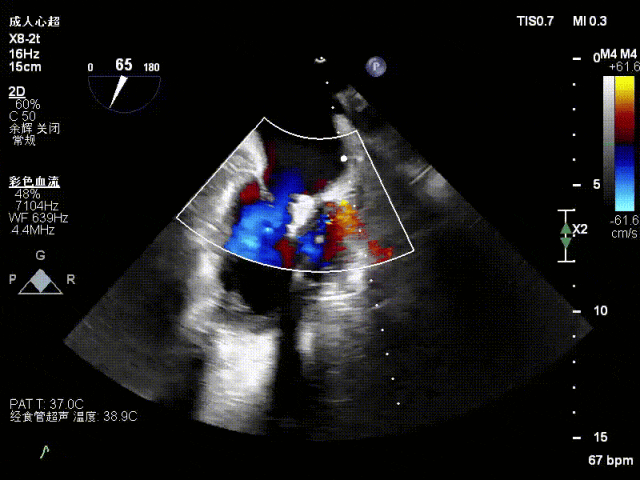

术前心超

退行性二尖瓣反流(DMR),P1/P2交界脱垂连枷(脱垂范围7mm,连枷间距4mm)

新分型:AAA型,MR 4+,VC:4×7mm

A1.5:20mm,P1.5:10mm,AP:30mm,MVA约3.8cm²

术中超声要点